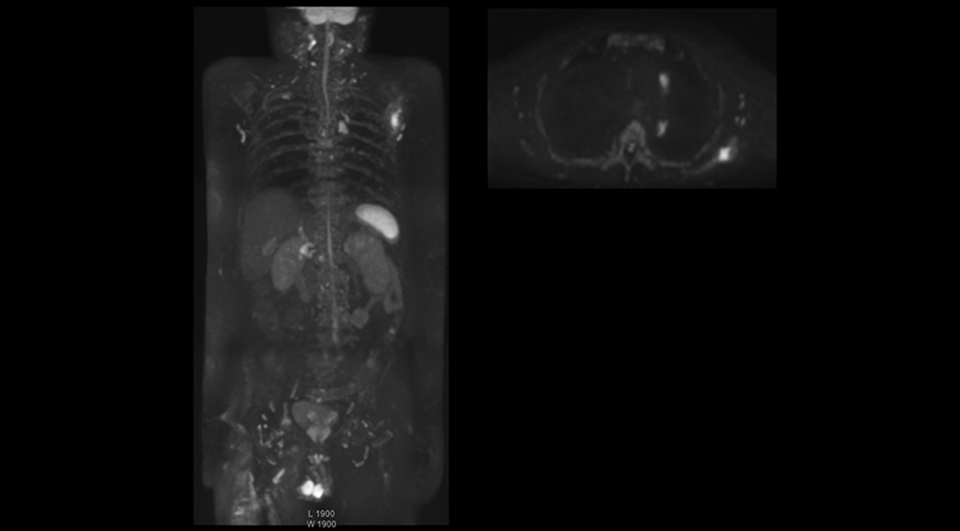

“Switching to coronal DWIBS – rather than axial – further shortens scan time,” says Mr. Naka. “Important is that a dS SENSE factor of 5 shortens exam time while high image quality can be maintained, thanks to Ingenia’s dStream architecture.” He adds that the coronal orientation also avoids artifacts that are specific to combining axial images.

“When we use a coronal DWIBS acquisition, we can perform a full whole body examination, including other required sequences, within 30 minutes,” he says.

After implementing the improved whole body protocol, the radiology team initially did not see a large increase in referrals, although Dr. Nobusawa saw clinical cases where the DWIBS images provided him valuable information for diagnosis. This is why Dr. Nobusawa and Mr. Naka started to actively educate referring physicians about the value of whole body DWIBS. They organized several presentations for physicians in the hospital, where they explained how DWIBS can be of value in oncology patients. The information it provides can be useful for physicians when staging cancer, as well as when determining or adjusting treatment strategy. Mr. Naka remembers some cases where DWIBS provided remarkable information. “In one example, DWIBS visualized bone lesions that could not be seen on PET or SPECT. In another case we had found a bone lesion when a normal L-spine scan for narrowing of the disk space was done. One extra DWIBS scan (2 stations, 8 minutes) demonstrated a lesion that later was confirmed to be the primary region of cancer.”